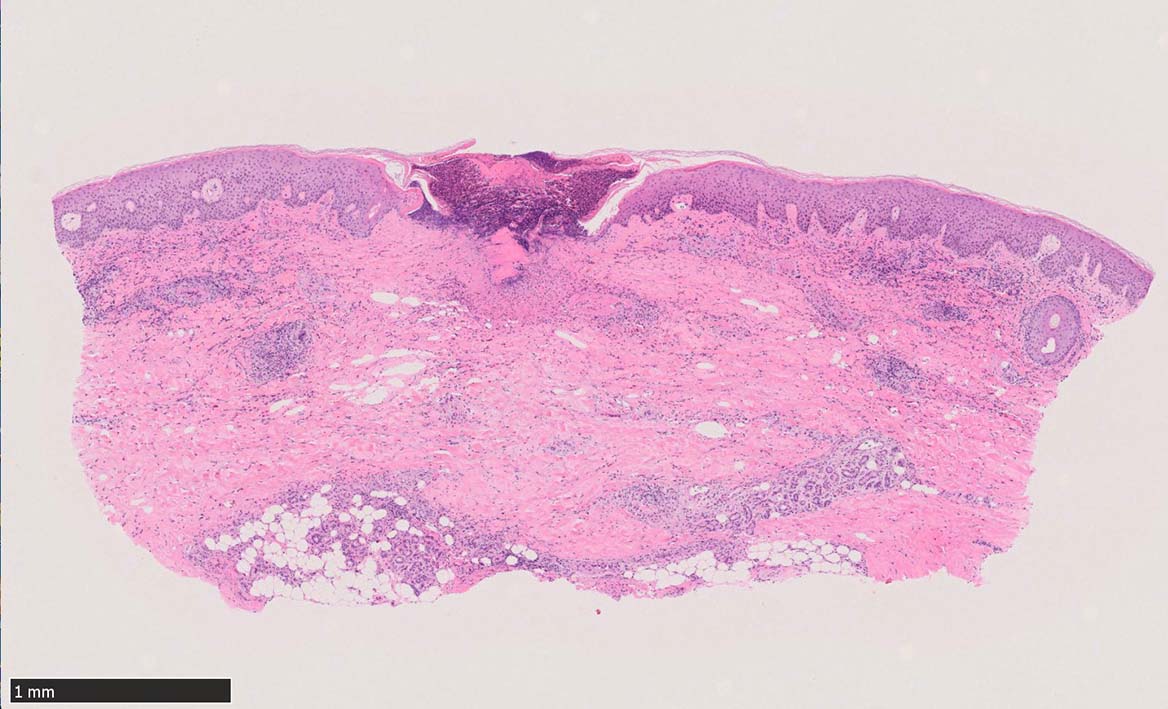

IWT-case03 マダニに咬まれた. 自分で虫体を除去したが傷がびらん化し, 発熱を来したため, 来院する.

痂皮の下に硝子様凝固物があり, 周囲には壊死組織が形成されている. 近傍の細血管には凝固物による閉塞の所見があるように見える. 連続する細血管には, fibrinoid necrosisを呈する壊死性血管炎が認められる.